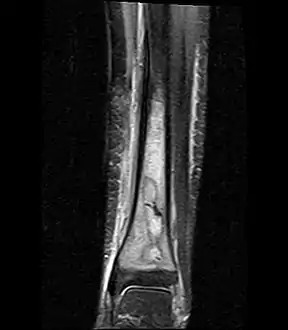

Coronal fat suppressed STIR image showing, bone marrow and subcutaneous edema as well as subperiosteal edema. The thin hypointense rim surrounding the intramedullary collection represents the reactive interface between the abscess and the body's attempt to wall it off. Coronal fat suppressed STIR image showing, bone marrow and subcutaneous edema as well as subperiosteal edema. The thin hypointense rim surrounding the intramedullary collection represents the reactive interface between the abscess and the body's attempt to wall it off.